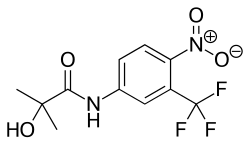

Антагонисты андрогеновых рецепторов часто используются при лечении заболеваний, вызванных избытком андрогенов, например, рака предстательной железы. Соединения, являющиеся полными или частичными антагонистами андрогеновых рецепторов, называют антиандрогенами. Полными антагонистами AR являются, например, нестероидные соединения гидроксифлутамид, нилутамид и бикалутамид. Некоторые соединения стероидной природы, например, ципротеронацетат и мифепристон, имеют как антагонистическое, так и агонистическое действие на AR[3]. Прогестины в высоких дозах могут блокировать андрогеновые рецепторы[55][56], поскольку андрогеновый рецептор наиболее родственен рецепторам прогестерона.

Селективные модуляторы андрогеновых рецепторов (SARM) оказывают влияние как на геномное, так и на негеномное действие андрогенов за счёт взаимодействия с ними в цитоплазме. Разработка таких соединений, которые модулируют биологическую активность AR тканеспецифичным образом, началась в 1999 году[3]. В настоящее время ведутся клинические испытания препаратов группы SARM энобосарма[57], действующего преимущественно на кости и мышцы, и LGD-4033[58].

Связывание AR c антагонистами, агонистами и прочими модуляторами вызывает в нём конформационные изменения, в результате которых набор корегуляторов (коактиваторов и корепрессоров), с которыми может взаимодействовать AR, изменяется. Таким образом, тканевая специфичность и селективность действия того или иного модулятора объясняется уникальным корегулятором, с которым может взаимодействовать рецептор после связывания с модулятором, а силу конечного ответа определяют уровни определённых коактиваторов и корепрессоров[3].